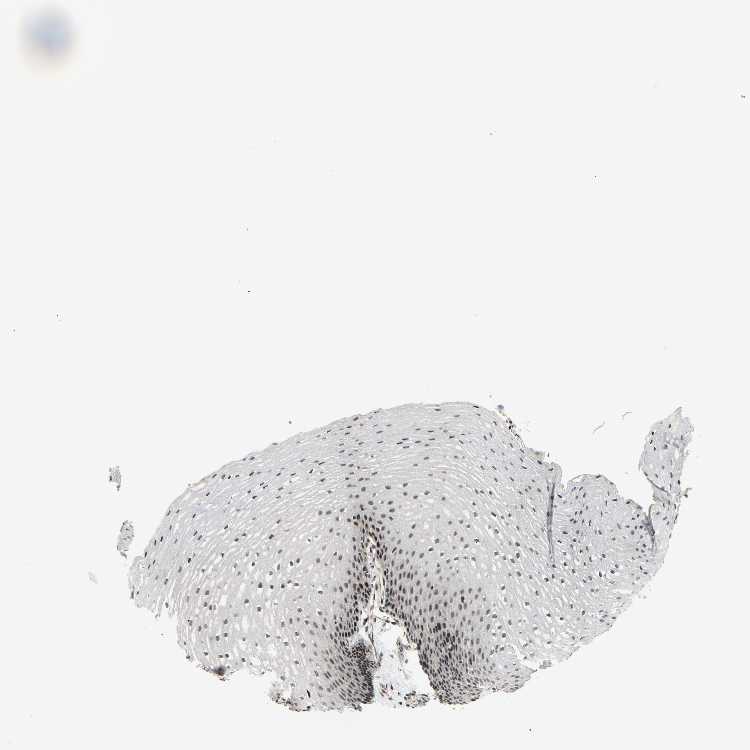

ESOPHAGUS - Antibody stainingi

Antibody staining in the annotated cell types in the current human tissue is reported as not detected, low, medium, or high, based on conventional immunohistochemistry profiling in selected tissues. This score is based on the combination of the staining intensity and fraction of stained cells.

Each image is clickable and will lead to virtual microscopy that enables deeper exploration of all samples and also displays staining intensity scores, fraction scores and subcellular localization as well as patient and tissue information for each sample.

Antibody HPA008758

Squamous epithelial cells High